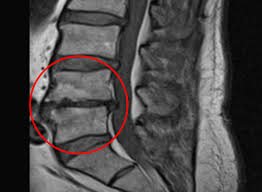

허리협착증은 척추 속 신경이 지나가는 통로인 '척추관'이 좁아지면서, 신경을 눌러 통증이나 저림 등의 증상을 유발하는 질환입니다.

- 요추관협착증은 주로 허리 부분(L3~L5)의 협착으로 인해 발생합니다.